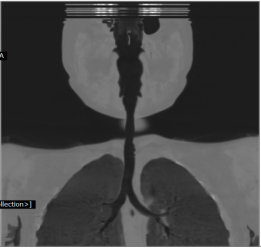

A 6-year-old female child presented to our clinic with progressive breathlessness and stridor for a duration of 5 days. She had a recent history of road traffic accident and sustained head injury and underwent craniotomy for extradural hemorrhage. Post-surgery she was on mechanical ventilator support for 10 days after which she was extubated. She developed stridor after 7 days of extubation. CT Neck revealed focal hour-glass configuration, concentric asymmetrical subglottic narrowing with associated soft tissue thickening 2-3cm below the level of vocal cords, with a diameter of 4.5 x 5.0 mm (AP X TR) at the point of maximal narrowing. Diagnostic flexible bronchoscopy showed circumferential stenosis (Grade III Myers-Cotton) of subglottic area about 2.5 cms below the glottis and we could not negotiate beyond the level of stenosis.

Rigid bronchoscopic repair of the stenosis was performed combining serial rigid bronchoscopic dilatations and balloon bronchoplasty using CRE dilatation balloons of varying sizes. Post dilatation, we were able to negotiate the rigid bronchoscope beyond the level of stenosis and were able to achieve a lumen of 100% with no residual stenosis. Follow-up CT Neck showed normal caliber of tracheal lumen with a luminal diameter of 8.6 x 8.3 mm at the level of previous narrowing. Total reduction of the clinical stridor was observed post procedure. Surveillance bronchoscopy after 4 weeks showed no further narrowing and good patency of tracheal lumen. Patient remained asymptomatic in subsequent follow up visits with improved pulmonary function tests

Radiology Images: